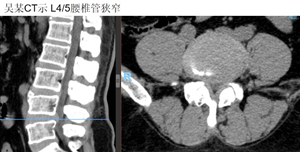

然后是吴某,双下肢疼痛麻木半年。入院肌间隙入路下L4/5肌间隙入路下腰椎融合手术。术后2天拔管,5天出院。

术后引流仅10ml。